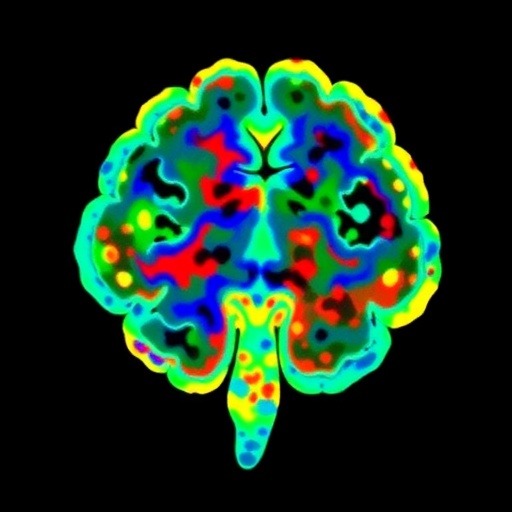

In this study, spearheaded by Habich, Baumann, Schwarz, and their colleagues, researchers employed imaging transcriptomics, a cutting-edge methodological framework that combines neuroimaging data with transcriptome maps. This approach helps pinpoint the locational alignment of gene expression patterns with observed cortical thinning and subcortical atrophy in DLB patients. By cross-referencing large-scale transcriptomic databases with structural MRI scans, the team delineated gene-brain atrophy correlations that shed light on region-specific susceptibilities.

Technological breakthroughs in multi-modal data integration underpinned the success of the study. High-resolution magnetic resonance imaging furnished precise quantifications of gray matter volume reductions, while publicly accessible brain transcriptome atlases enabled comprehensive gene expression mapping. Sophisticated bioinformatics pipelines coupled these datasets, allowing robust statistical inference while mitigating confounding factors such as age-related changes and comorbidities.